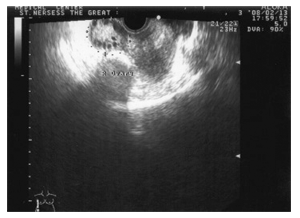

Третий тип эхограммы яичников определялся у 51,0% (24) больных с АО. Структура яичников опять отличалась повышенным уровнем эхогенности. В максимальном эхографическом срезе выявлялось 7-8 жидкостных структур диаметром 0,6-0,7см. Граница между мозговым и корковым веществом яичников прослеживалась отчетливо; фолликулы располагались по всей протяженности коркового слоя,поверхностно, создавая неровность эхографического контура яичников. AFC низкий – 7- 8. Установлено, что признаки созревания фолликулов определялись на 10 день цикла только у 42% больных с АО с третьим эхографическим вариантом (в основном при опсоолигоменорее и с сохраненным ритмом менструаций). У 27,6% пациенток наблюдалось неполноценное созревание доминантного фолликула, в 38,2% случаев–кистозная или облитерационная атрезия неовулировавшего фолликула, и только у 14,8% женщин были констатированы спорадические овуляции. Темп роста доминантного фолликула достоверно (р‹0,05) отставал от показателя в контрольной группе (0,3±0,04 см/сутки) и составил 0,12±0,02см во время овуляторного цикла, 0,08±0,02см/сутки при облитерационной атрезии и 0,17±0,01см/сутки при кистозной атрезии. По эхографическим данным длительность существования зрелого фолликула до возможного исхода достоверно (р‹0,01) превышала аналогичный показатель в контрольной группе (4,1±0,03 дня) и составила, соответственно, 6,2±0,06 дня; 8,7±0,05 дня и 18,8±0,2 дня. Максимальный диаметр доминантного фолликула составил 1,7см (по сравнению с 2,3см у здоровых женщин) (рис. 3).

Рис. 3. III тип эхограммы яичников и ее схематическое изображение. Преимущественное расположение фолликулов в корковом слое, отчетливо отграниченном от мозгового; на 10 день менструального цикла — отсутствие доминантного фолликула